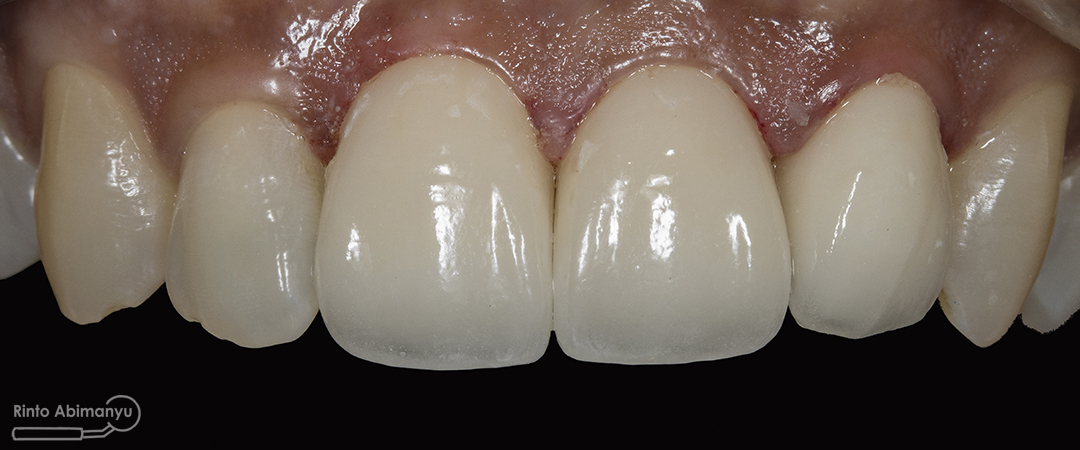

Foto klinis gigi-gigi anterior yang mengalami fraktur

Begini kondisi klinis saat datang…

Nah ini resume foto before dan after perawatannya…